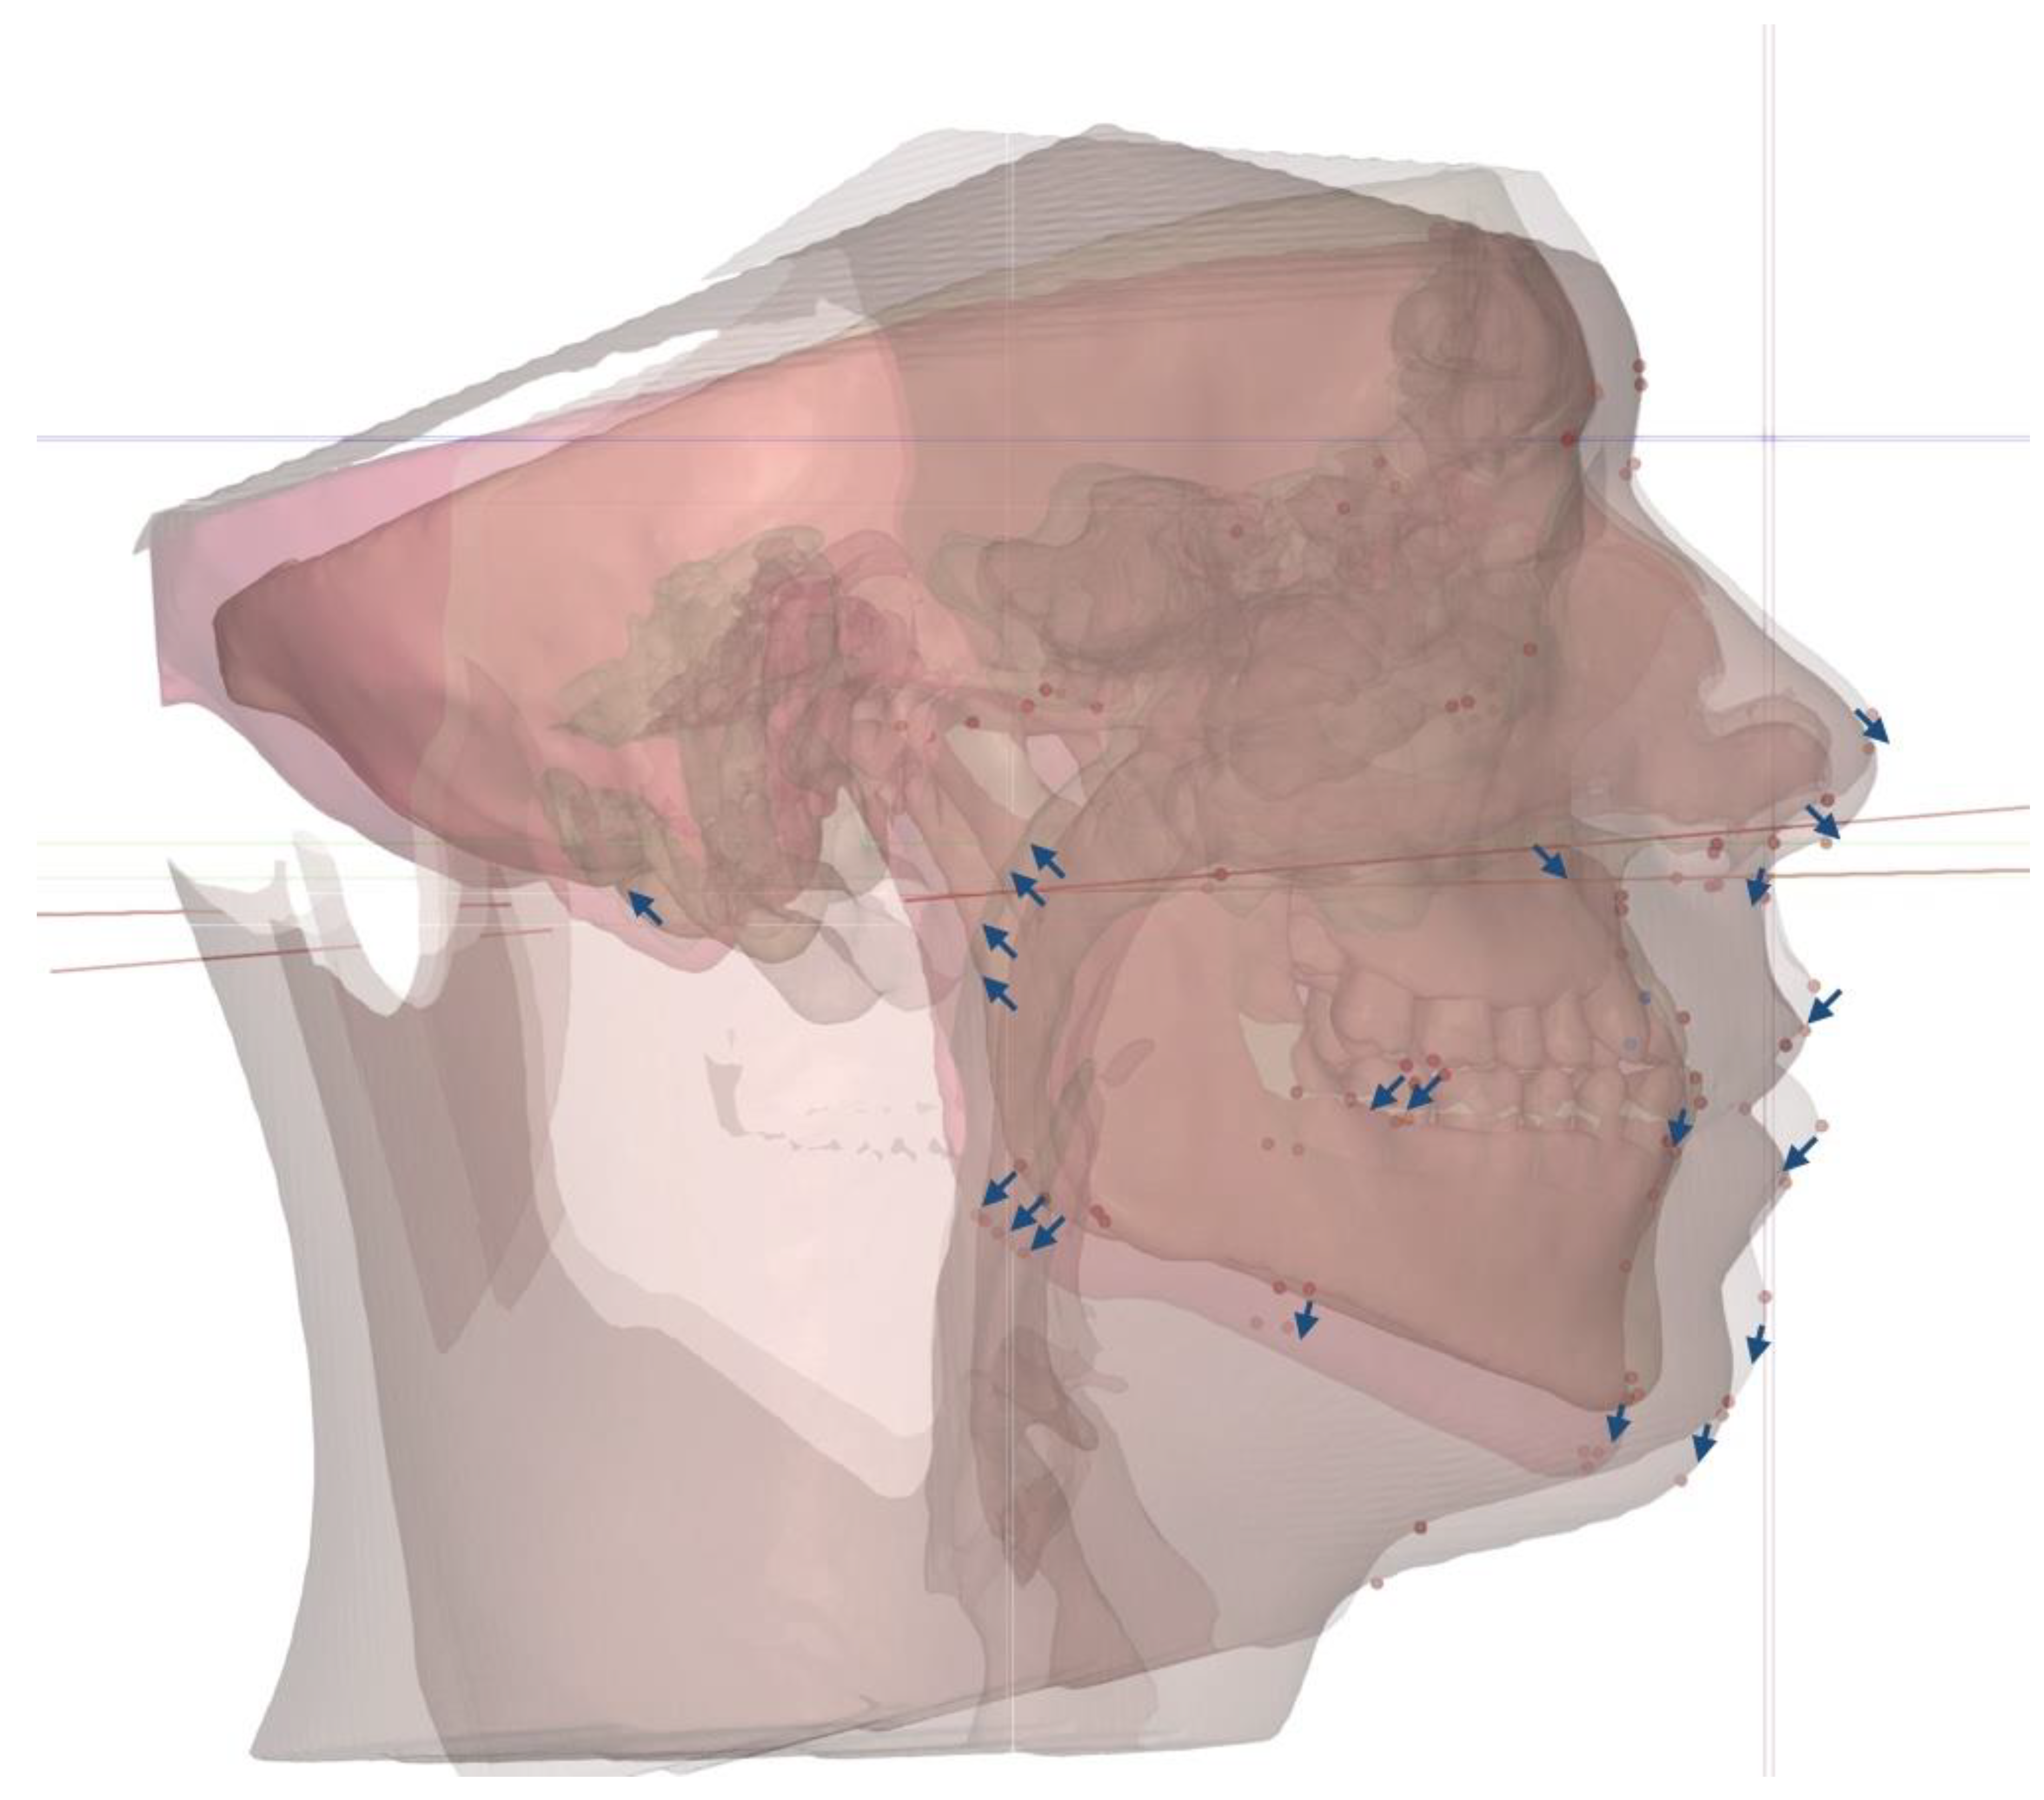

The total vectors of the 3D changes introduced via 3D-guided midpalatal piezocorticotomy-assisted MARPE are described in Fig. 6.

Figure 6. Total vectors of the 3D movements of the facial skeletal structures with 3D-guided midpalatal piezocorticotomy-assisted MARPE.